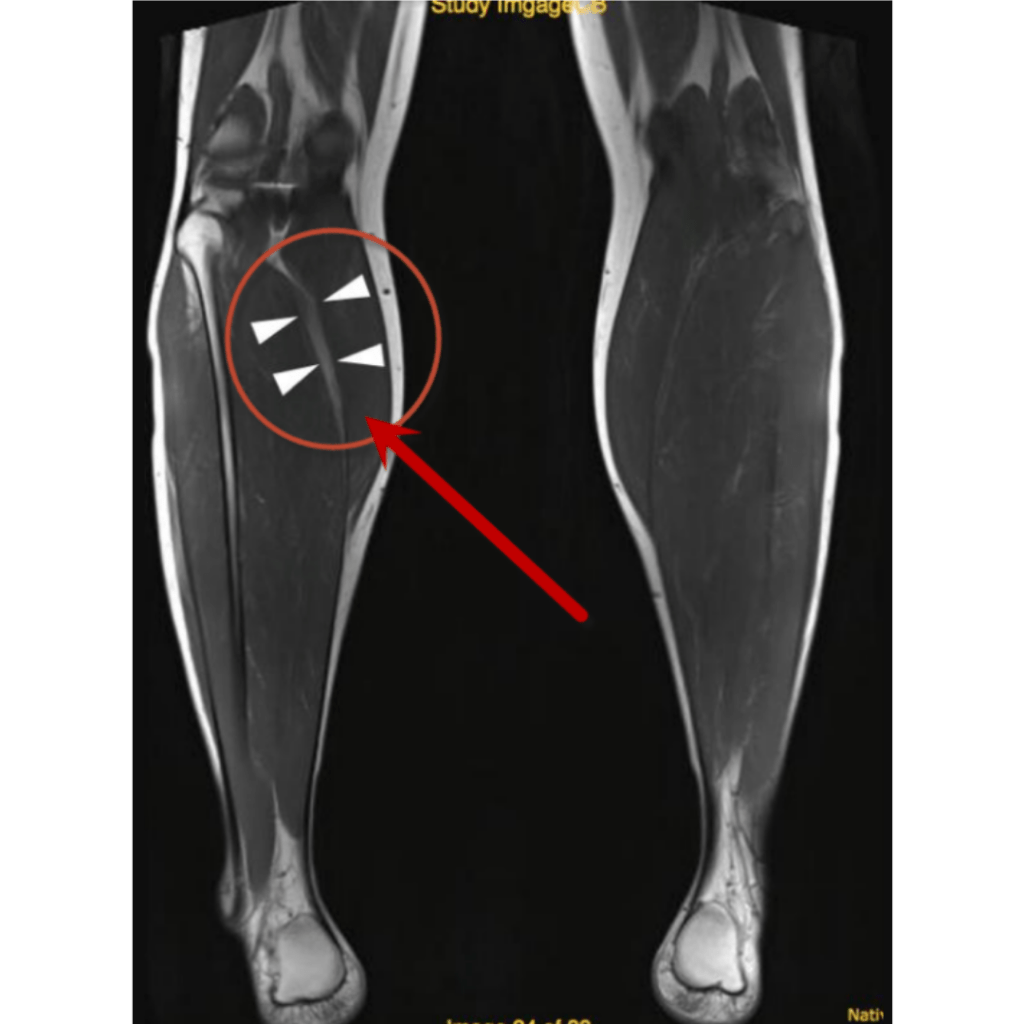

El diagnóstico de esta afectación dependerá mucho de su localización, en caso de sospecha de compromiso en un músculo superficial se puede hacer uso de ecografía (ultrasonido), en tejidos más profundos es más eficiente una resonancia magnética.

Resonancia magnética Ruptura parcial Grado II

Un desgarro de segundo grado en el gemelo medial (músculo de la parte interna de la pantorrilla) el cual no necesito un tratamiento quirúrgico.Por lo que fue referido para su recuperación con terapia física.